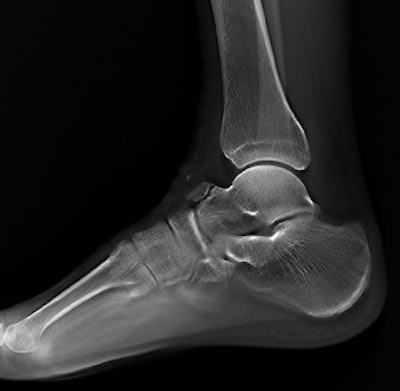

The machine can record static, dynamic, and real-time 3D sequences, and the full range of its potential applications is still to be explored. But there are clinical applications in which it already appears to have advantages over CT, notably in investigations of upper limb fractures in obese patients and weight-bearing lower-limb bone examinations of diabetics, he added.